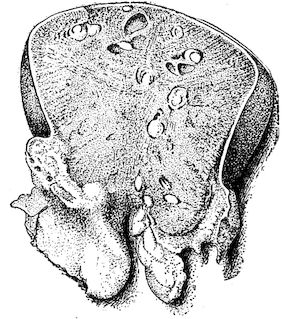

Fig. 5.—Head of a pig suffering from osseous cachexia.

Fig. 8.—Transverse section through the middle region of the face in a pig suffering from osseous cachexia.

18In the final stages, the bones may be cut with a knife, and a time arrives when bony tissue seems completely to have disappeared; thus, as shown in Fig. 8 herewith, it was possible to cut the entire head of a pig into thin slices without the slightest difficulty. All parts of the head had been affected by the softening change.